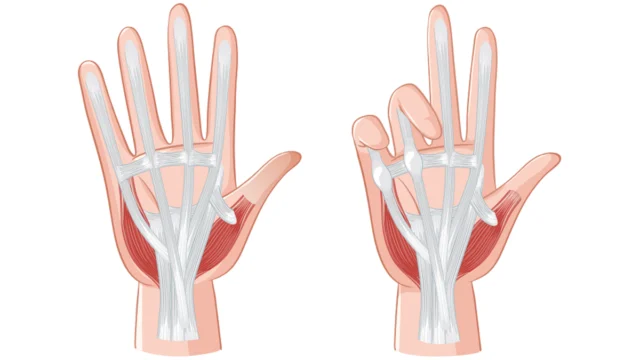

Dupuytren Kontraktürü Nedir?

Dupuytren Kontraktürü Nedir?